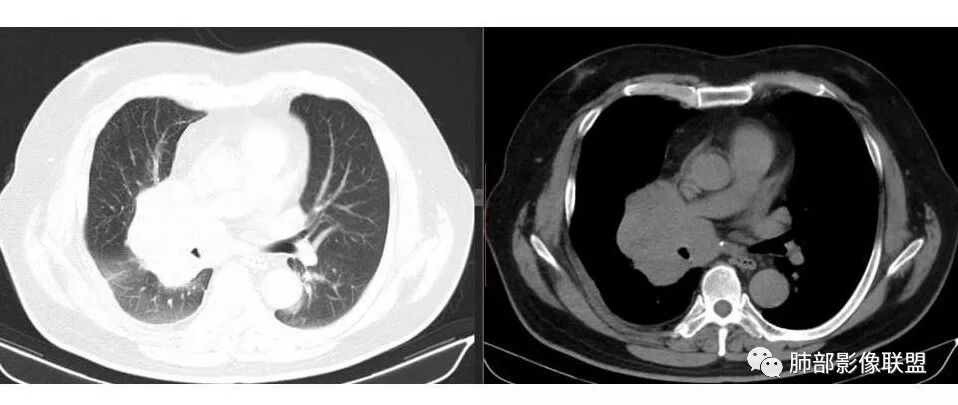

1.右肺上叶不规则结节影,右肺门及纵隔多结节并形成巨大块影,密度均匀,沿途支气管明显狭窄。

原发灶小或隐匿,肺门纵隔淋巴结异常增大,所谓“娘小崽大”常见于肺小细胞癌!

2.右肺小叶间隔增厚伴微小结节,提示癌性淋巴管炎。